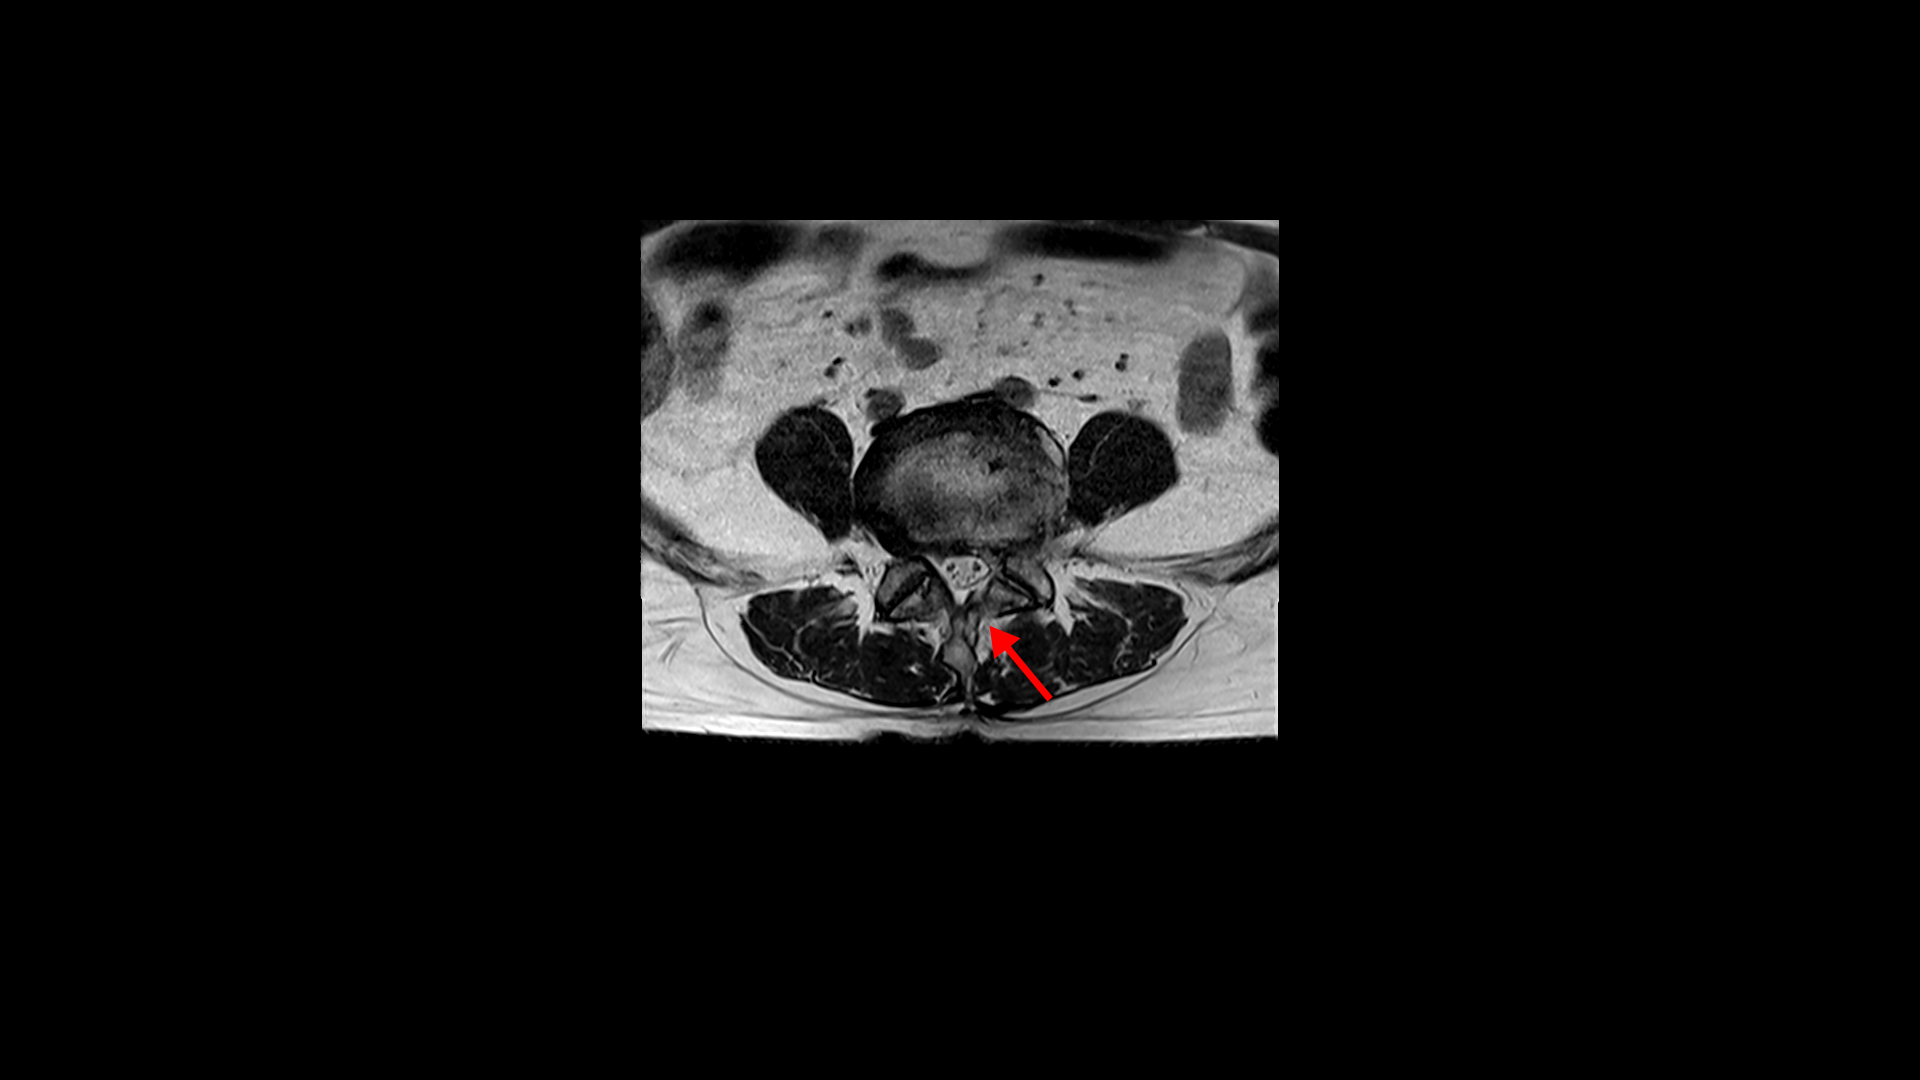

허리MRI를 보면 두 마디의 퇴행성디스크와 추간공협착이 있습니다.

4번 5번은 왼쪽 신경이 빠져나가는 추간공이 뼈가 자라면서 좁아져 추간공협착이 있습니다.

또 왼쪽 후궁에는 과거에 받은 수술의 흔적도 보입니다.